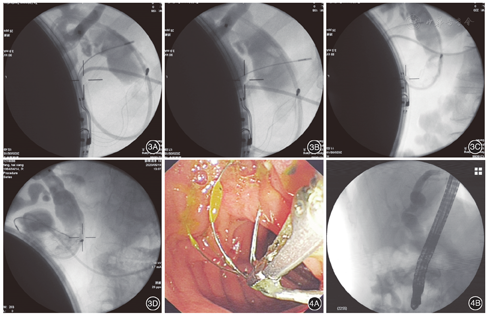

患者女,56岁,因"反复上腹痛半年,再发伴加重2周"入院。患者2周前因腹痛在当地医院就诊,查上腹部CT及磁共振胰胆管成像(magnetic resonance cholangiopancreatography,MRCP)提示胆总管巨大结石,肝内外胆管扩张,ERCP检查示胆总管巨大结石,予ERCP+经内镜乳头括约肌切开术(endoscopic sphincterotory, EST)+取出部分结石+经内镜鼻胆管引流术(endoscopic nasobiliary drainge,ENBD),为进一步取石带鼻胆管来我院。入院查体:体温36.7℃,血压95/61 mmHg(1 mmHg=0.133 kPa);皮肤巩膜无黄染,腹软,中上腹压痛,无反跳痛,余未见明显异常。入院后辅助检查:白细胞数5.3×109/L、中性粒细胞数2.6×109/L、C-反应蛋白2 mg/L;丙氨酸氨基转移酶78 U/L,门冬氨酸氨基转移酶68 U/L,γ-谷氨酰基转移酶365 U/L,碱性磷酸酶109 U/L,总胆红素21.2 μmol/L;肾功能、电解质及凝血指标等均正常。考虑诊断:困难胆总管结石ENBD术后;肝内外胆管扩张。入院后予ERCP造影见胆总管约2.0 cm×2.5 cm巨大结石(图1)。予以柱状气囊1.2~1.5 cm,压力4 ATM,扩张约2 min,用碎石网篮机械碎石后取出大量结石,再次以螺旋网篮清扫残余结石时发生网篮嵌顿断裂(图2),因断端较短,无法紧急镜内碎石,予以留置鼻胆管后行3次ESWL,冲击波冲击共计17 933次,总能量710.80 J(图3)。再次ERCP时以异物钳顺利取出网篮断端,并取净结石(图4)。